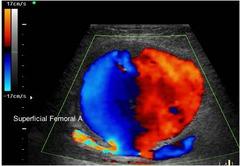

Varicocele

left side

most common correctible cause of male infertility

Varicocele